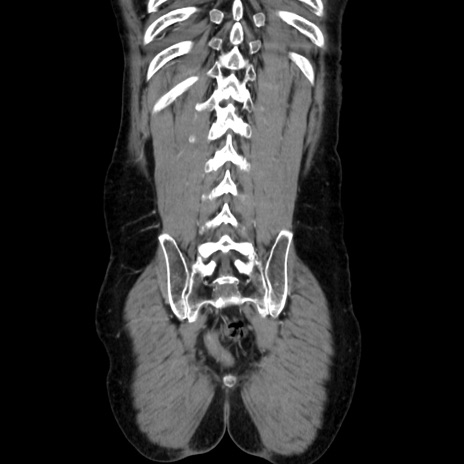

症例37(冠状断像)

【症例】40歳代 男性

【主訴】腹痛

【現病歴】4時間ほど前に電車に乗車中に臍部上より腹痛出現。徐々に増悪し起立困難となり、救急外来受診。生ものは数日食べていない。今朝お雑煮を食べた。

【身体所見】BT 36.8℃、BP 117/84mmHg、HR 91/min、SpO2 97%、苦悶様、腹部:臍上部広範囲圧痛あり、反跳痛±

【データ】WBC 8100、CRP 0.03